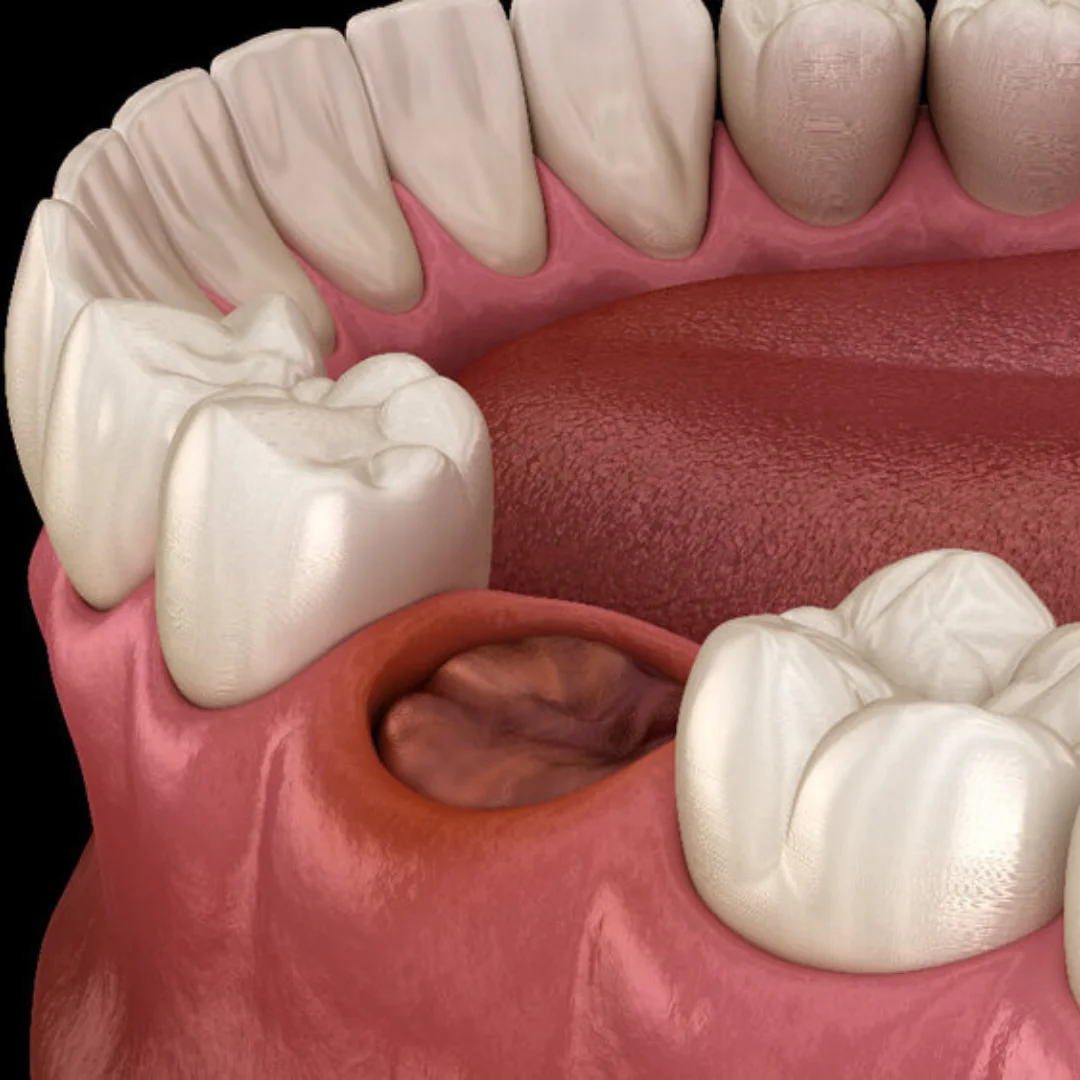

What is a Dry Socket?

After a tooth extraction, especially for wisdom teeth, a blood clot should form in the socket. This clot protects the bone and nerves underneath. If this clot is lost or dissolves too soon in the first 24 hours, it can expose the bone. This can lead to a dry socket, which is a dental emergency. A dry socket causes severe pain and needs urgent care.

- Empty-looking socket where the tooth was removed

- Visible bone in the extraction site